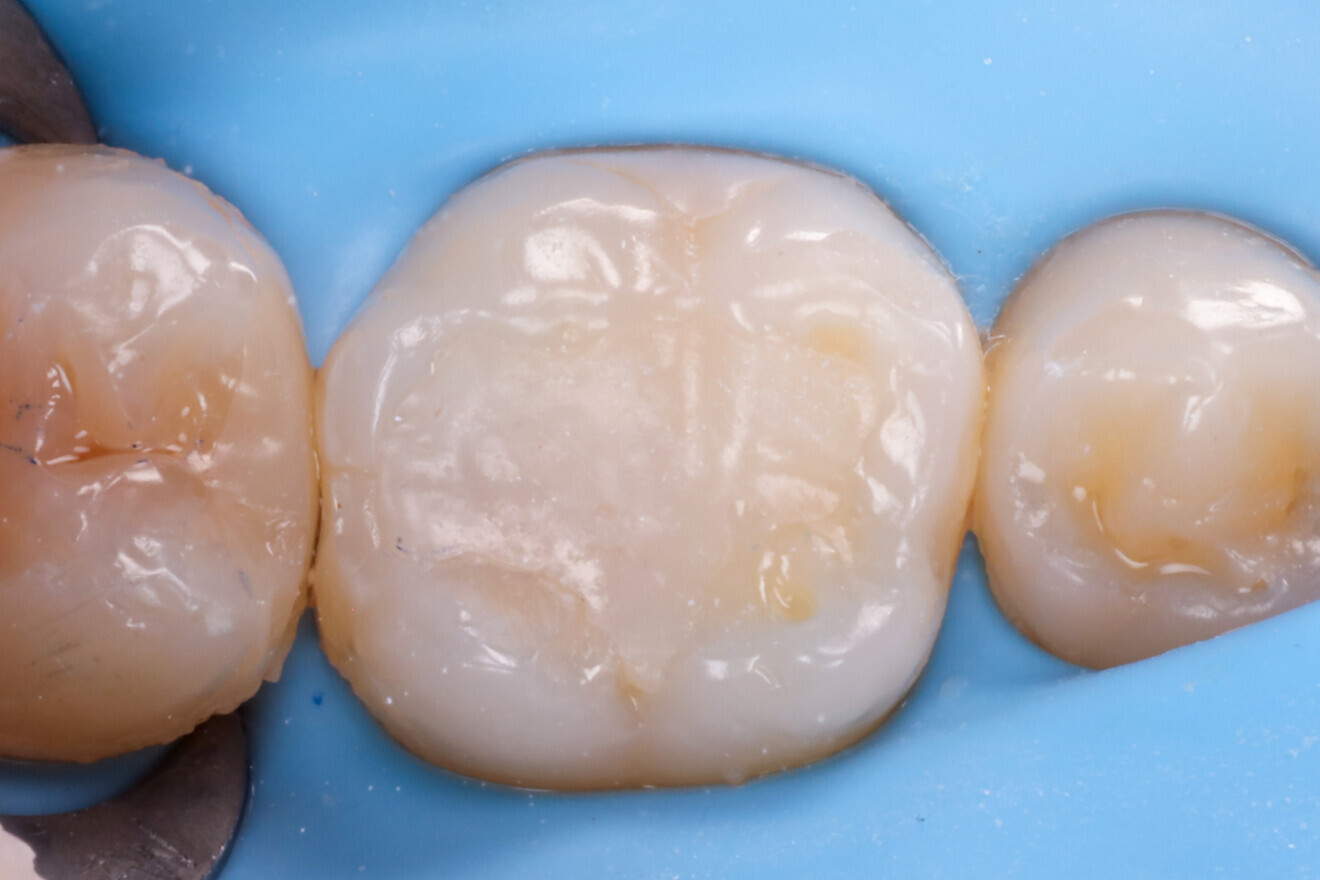

After try-in (Fig. 22), the restoration was bonded using a low-flow, highly filled composite (Estelite Universal Flow, SuperLow; Fig. 23). Excess material was removed (Fig. 24), followed by another round of light polymerisation for 20 seconds per side. Final excess removal was done (Fig. 25), and thanks to the preformed anatomy, most of the morphological detail remained intact even after occlusal adjustment (Fig. 26). A control radiograph was taken (Fig. 27).

Fig. 25: After excess removal and polishing of the restoration.